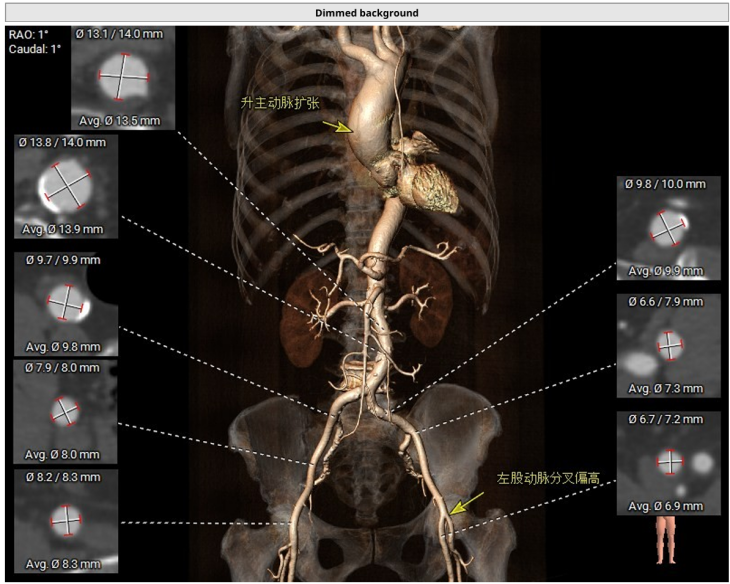

更棘手的是,王奶奶的主动脉弓部像打了个 「急转弯」,血管又短又弯,加上她本身心室小,又有冠心病、高血压,传统开胸换瓣手术风险极高,就像在 「钢丝上跳舞」。

夏淑东主任团队经过详细评估,决定为她实施经导管主动脉瓣置换术(TAVR)。这种手术不用开胸,只需要在大腿根部的股动脉开一个小口子,就像用一根 「魔法导管」 把新瓣膜送到心脏里。

手术使用目前最先进的「球扩瓣」 瓣膜,瓣膜小、容易过弯,具有优秀的输送性及释放稳定性,能很好地在王奶奶的「急转通道」里安全穿梭。

手术当天,夏淑东主任先从右侧股动脉穿刺置入血管鞘,在血管里搭建了一条 「临时通道」。接着用 20 mm 的球囊对狭窄的瓣膜进行预扩张,仿佛用打气筒把生锈的阀门稍微撑开一点。

最关键的一步是输送瓣膜过弓。王奶奶的主动脉弓严重弯曲,团队凭借精湛的技术,让装载着瓣膜的输送系统顺利 「过弯」 并跨瓣。瓣膜定位后,医生精准释放了 23 mm 的人工瓣膜,在正确的位置安装好了新的 「心门」。